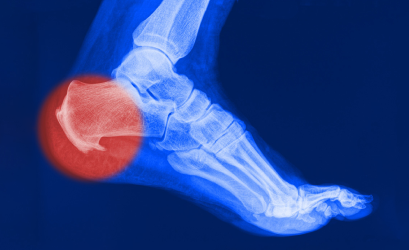

Подошвенной фасцией называют жесткую сухожильную пластинку, которая прикрепляется к пяточной кости и головкам плюсневых костей, создавая своеобразный защитный чехол для подошвенной поверхности стопы. Она помогает поддержанию формы ступни и свода стопы. Нормальная анатомия стопы устроена так, чтобы человек при ходьбе не ощущал боли - для этого имеется подошвенный апоневроз, который играет роль амортизатора (мостика) для свода стопы. Подошвенная фасция натянута как тетива между костями и при каждом шаге эта своеобразная тетива натягивается, удерживая свод стопы, не давая костям стопы «разъехаться».

К сожалению, избыточный вес, повышенные физические нагрузки, высокие каблуки или тесная модельная обувь, плоскостопие приводят к тому, что подошвенная фасция в процессе ходьбы перерастягивает и травмируется, возникают микроповреждения волокон, воспаление.

Воспаление приводит к образованию отека, прорастанию микрососудов и мелких нервных веточек в поврежденную фасцию, возникает боль. Особенно сильно боль проявляется после ночного сна и покоя, так называемая «стартовая боль». Оставшиеся неповрежденными волокна подошвенной фасции начинают работать вместо разорванных, испытывая повышенную нагрузку, и тоже повреждаются. Воспаление и боль прогрессируют, заставляя снизить нагрузку.